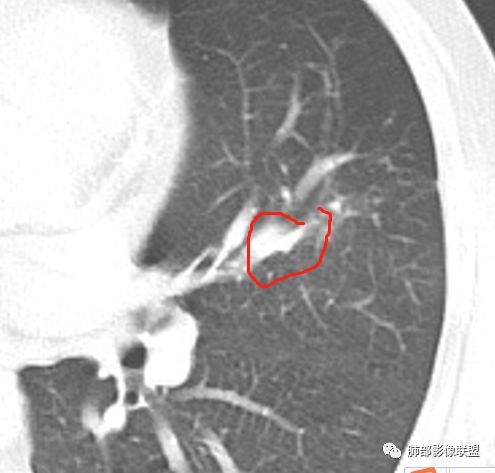

几个结节

下面这一支堵了

前后对比,这些结节其实是没引起支气管远端病变的

南大标注,这几个确实结节没有阻塞支气管,感觉是在血管分叉地方。

@南边 关键是上面这几个结节有的密度度,有的密度低。与下面堵塞支气管的结节样改变是否不是一回事,

如果下面堵塞是恶性,那上面的是不是考虑转移?另外一年结那个疑似结节的地方与现在堵塞的地方好象不一致。